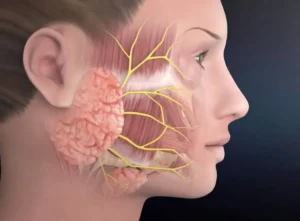

الأورام النكفية هي نمو غير طبيعي للخلايا يبدأ في الغدد النكفية. وتتكون العدد النكفية من غدتين لعابيّتين تقعان أمام الأذنين مباشرة واحدة على كل جانب

أورام الغدد اللعابية هي نمو غير طبيعي للخلايا يبدأ في الغدد اللعابية. وتتميز أورام الغدد اللعابية بندرتها. تفرز الغدد اللعابية اللعاب. ويساعد اللعاب على الهضم